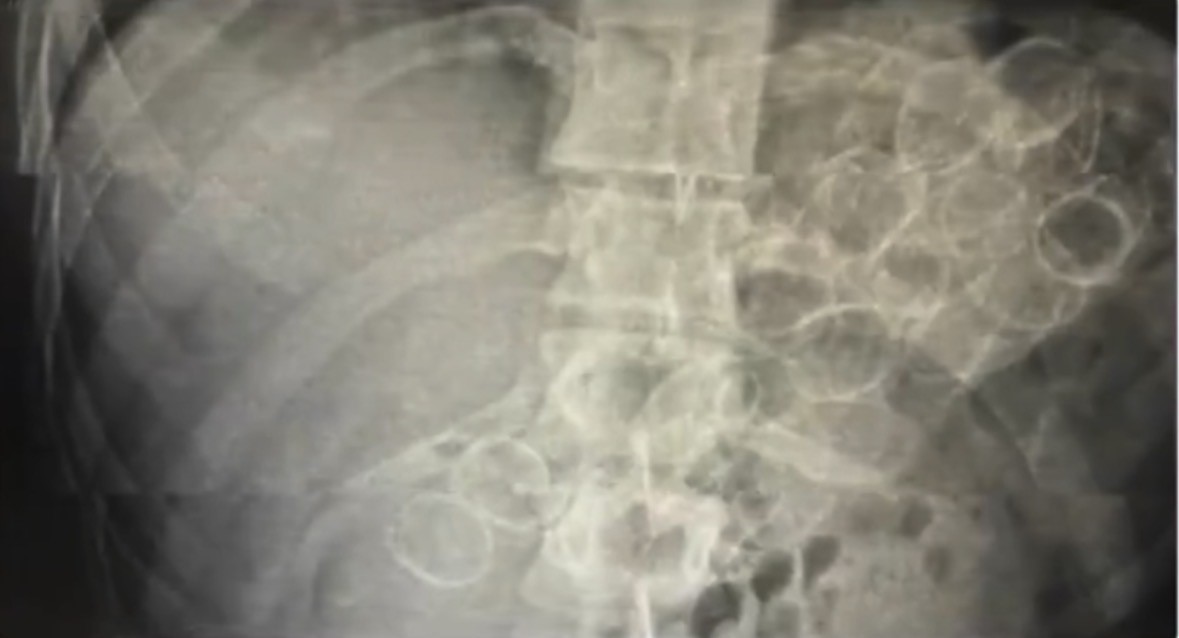

Bingöl İl Emniyet Müdürlüğü Narkotik Suçlarla Mücadele Şube Müdürlüğü ekiplerince yürütülen çalışmalar neticesinde, "Uyuşturucu veya Uyarıcı Madde Ticareti" suçu kapsamında 3 şahsın "yutma ve tıkma" yöntemiyle mide ve bağırsaklarında yüklü miktarda uyuşturucu madde taşıyarak kente getirdiği belirlendi. Ekipler tarafından yakalanan şüphelilerin hastanede yapılan tedavileri sonucunda, toplam 75 kapsül halinde 775 gram metamfetamin maddesi ele geçirildi.